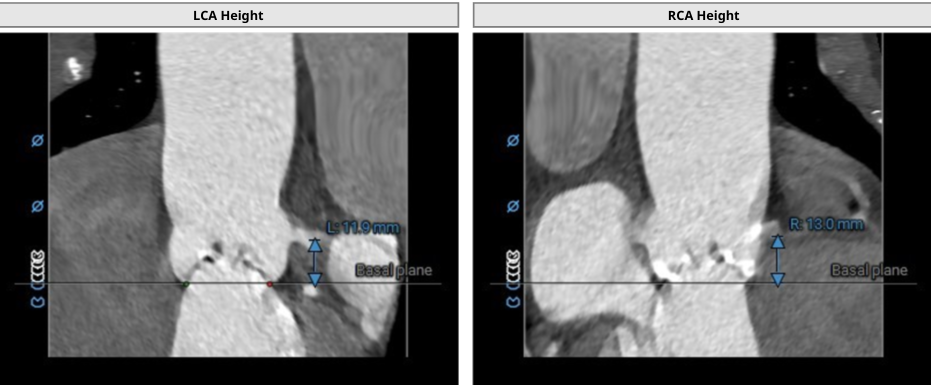

冠脉风险评估-左右冠脉风险不高